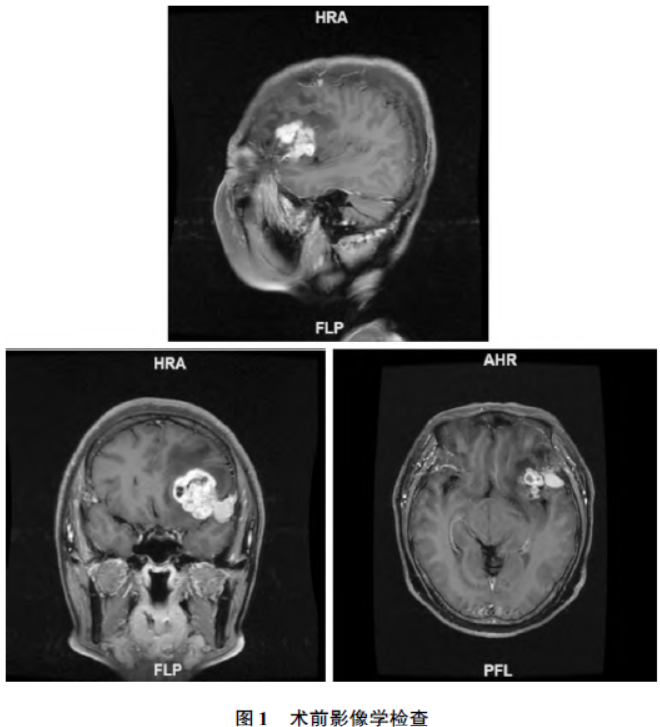

神经系统查体未见特殊异常。头颅核磁共振成像

(magnetic resonance imaging,MRI)检查提示左额叶见团块状混杂信号,增强后肿瘤实体由两部分组成,一部分呈不均匀花环样强化,另一部分基底较宽,密度均匀一致,“脑膜尾征”阳性。左侧脑室受压,中线结构局部右移。考虑高级别胶质瘤合并脑膜瘤(图1)。患者颅内占位诊断明确,连云港市第一人民医院神经外科科内讨论后决定予以手术治疗。

本研究中患者的影像学检查显示出颅内多发原发肿瘤的典型特征,这些特征符合高级别胶质瘤和脑膜瘤的表现。术前影像学的诊断与术后的病理结果相一致,从而得出了诊断。尽管组织病理学是临床诊断的“金标准”,但在获得病理结果之前,影像学检查在疾病的早期诊断及鉴别诊断中发挥着至关重要的作用。